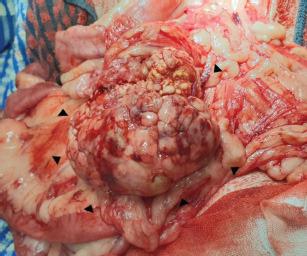

Surgical resection of the mass and damaged pancreatic vessels was performed. Adherent mesenteric blood vessels and a segment of the jejunum were also removed due to their association with the mass, followed by jejunal anastomosis. No abnormal clinical signs were observed postoperatively. A definitive diagnosis of pancreatic acinar cell tumor was made based on histopathological findings. The patient remained clinically stable without evidence of recurrence for over 11 months after surgery.

This report is the first documented case describing successful surgical management of nontraumatic hemoperitoneum secondary to pancreatic acinar cell carcinoma in a dog. Histopathological evaluation confirmed a moderately well-differentiated pancreatic acinar cell carcinoma. This case suggests that timely diagnosis and intervention may improve outcomes in patients with hemorrhagic presentations of pancreatic neoplasia.